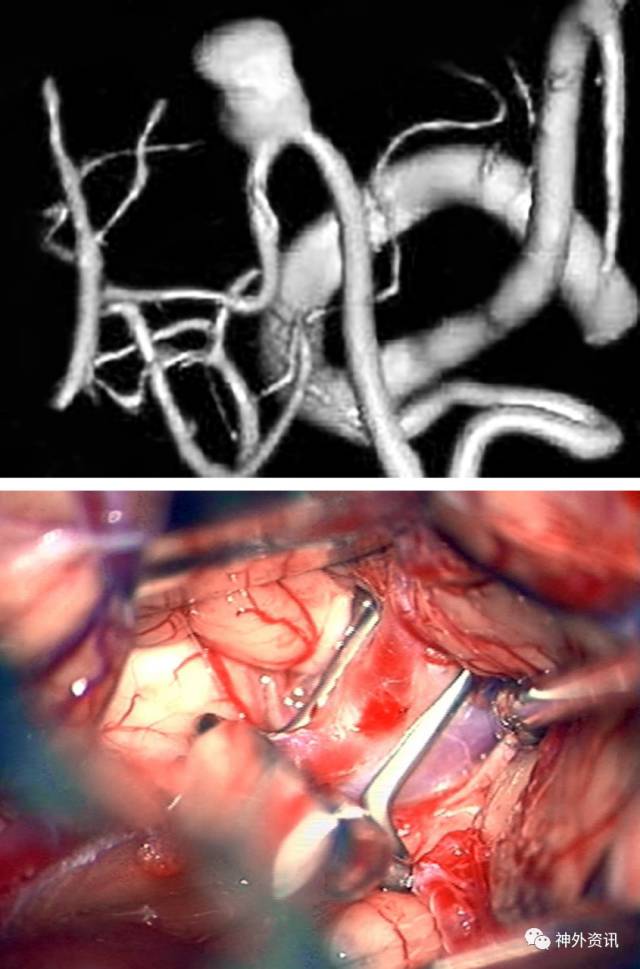

图1:上图显示的是中线附近的PICA动脉瘤。左下图显示的是更加经典的近心端PICA动脉瘤,右下图显示的是远端脉络膜前动脉瘤也出现在同一个病例中。值得注意的是PICA在动脉瘤颈处起源。

图11:PICA动脉瘤可以根据其所处的解剖结构直接夹闭。椎动脉近心端临时阻断(上图),椎动脉远心端用红色箭头标记(下图)。

图12:右侧PICA动脉瘤使用直角动脉瘤夹夹闭(上图);远端和近端需要临时阻断,原因在于怀疑可能是假性动脉瘤(中图);最终夹闭动脉瘤(下图)。

图13:更加典型的PICA动脉瘤被完全夹闭,使用直角跨血管夹(上图);椎动脉远端用红色箭头表示,动脉瘤使用*标记(中图);舌下神经与PICA、VA的关系被显示出来;最终动脉瘤被夹闭,箭头所示为动脉瘤夹所在位置(箭头,下图)。